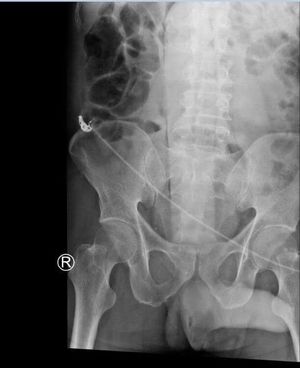

40 y.o male came to ER SOB and c/o abdomen pain. Did not say why. Xray showed this! It tried to be removed via procedural sedation however object was too large, so pt went to OR to get it surgically removed. Doubt he will be using that anymore. Haha

We send our dildo to pathology as a specimen. ..one that size really distorts the normal anatomy of the colon!!!